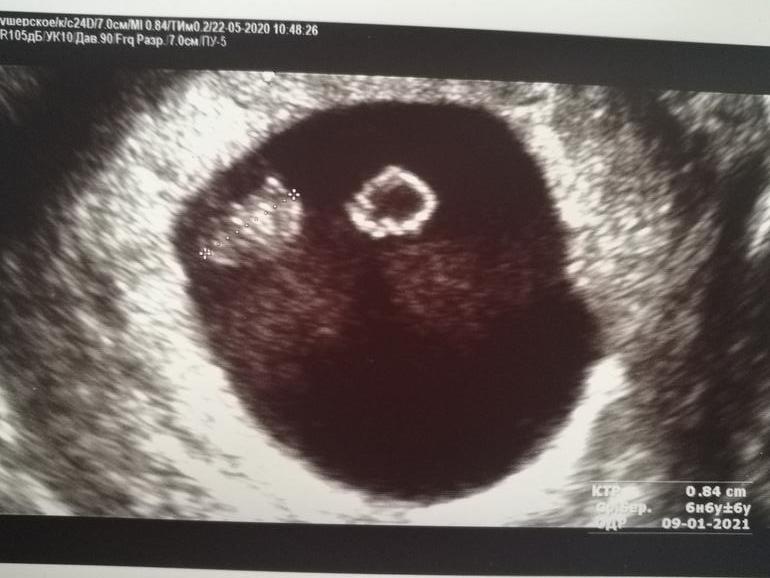

МалышикВчера сходила снова на УЗИ (срок по мс был 7.4)

И правда, на фасолинку малыш похож, как и в календаре написано.

Ктр 8,4мм, сердцебиение 150!

Сердечко не только слышала, но и видела.

Сказал, что всё хорошо, только тонус небольшой (пешком шла, так наверно от этого). Срок поставил 6,6 (пдр 9 января).